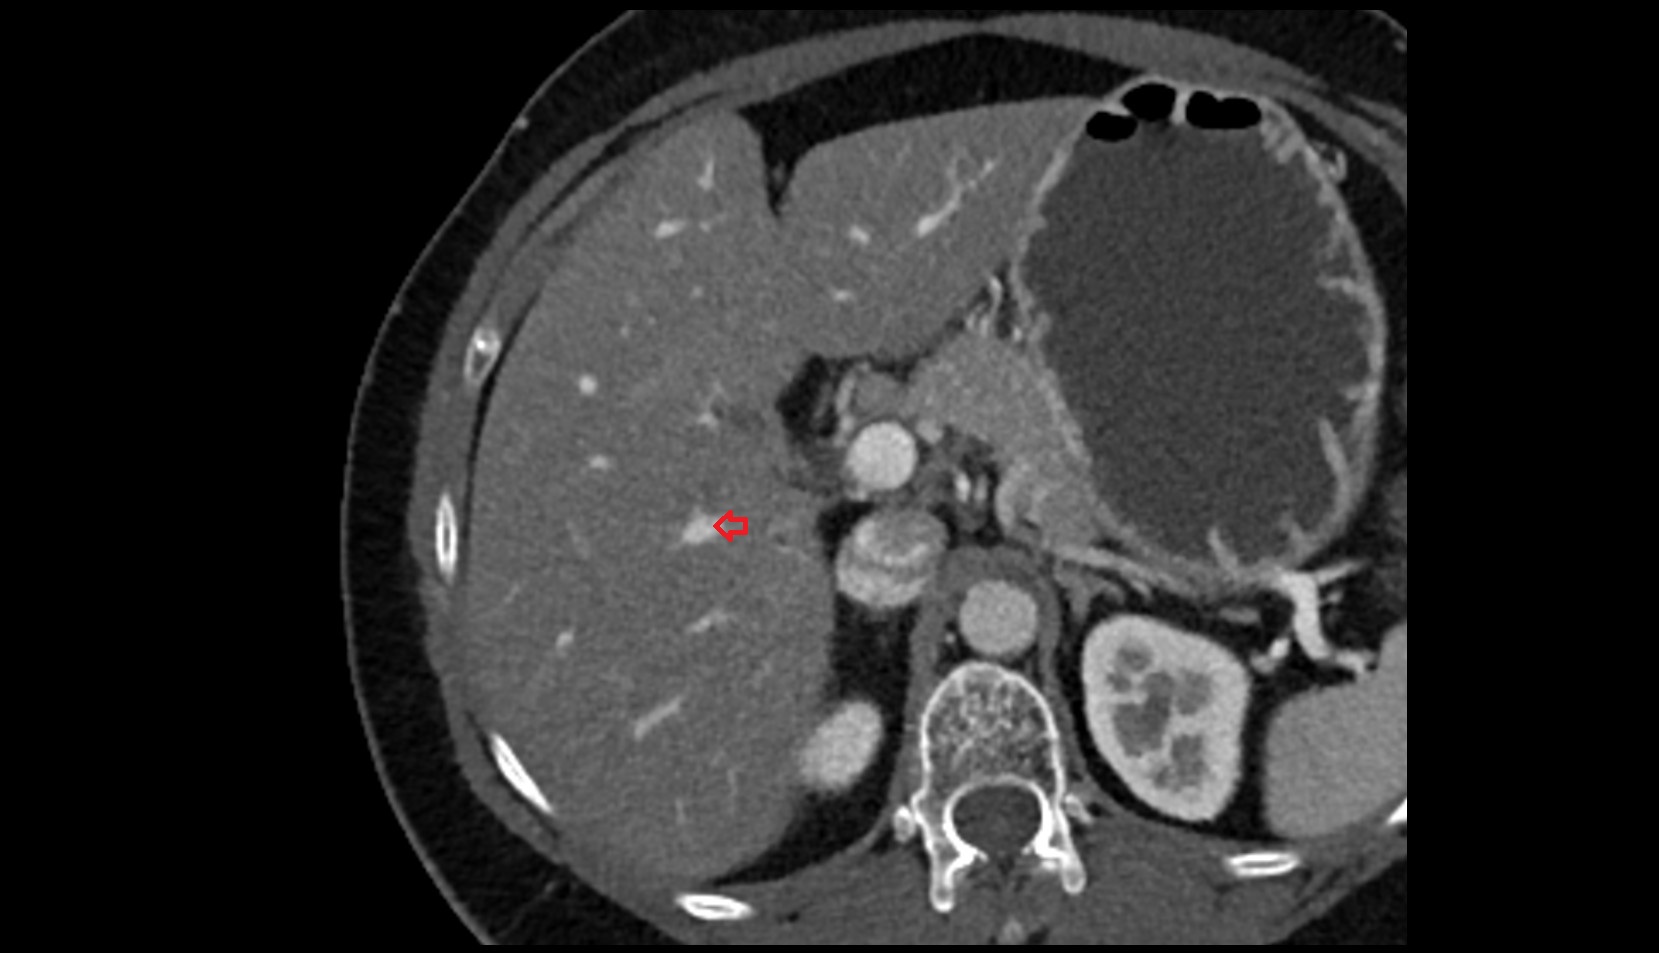

- Right lobe of liver

- Liver

- Liver Segment I – Caudate lobe

- Liver Segment II – Left lateral superior segment

- Liver Segment III – Left lateral inferior segment

- Liver Segment IVa – Left medial superior segment

- Liver Segment IVb – Left medial inferior segment

- Liver Segment V – Right anteroinferior segment

- Liver Segment VI – Right posteroinferior segment

- Liver Segment VII – Right posterosuperior segment

- Liver Segment VIII – Right anterosuperior segment